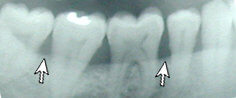

This patient has Periodontitis. Notice the bone deterioration and uneven level of bone.

Healthy gums and bone.